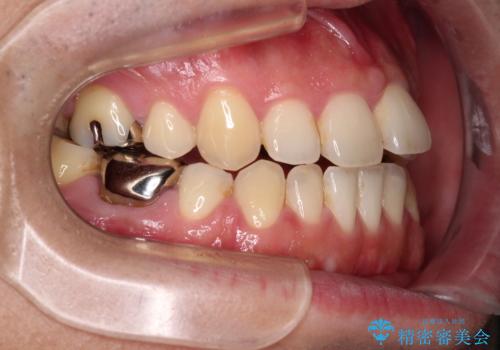

- 抜歯矯正の後戻りを気にして来院された患者様です。

舌の突出癖によるオープンバイトになり、前歯の叢生が後戻りしていました。

舌のトレーニングを行いながら、インビザラインを用いて矯正治療を行うこととしました。

インビザラインの特性を活用して奥歯の咬み合わせを圧下させることで、前歯のオープンバイトを改善さえることができました。